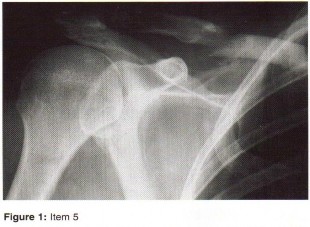

ORTHOPEDIC MCQS ONLINE BANK OITE 97 97.1 A 55-year-old woman reports a spontaneous onset of severe pain in he…